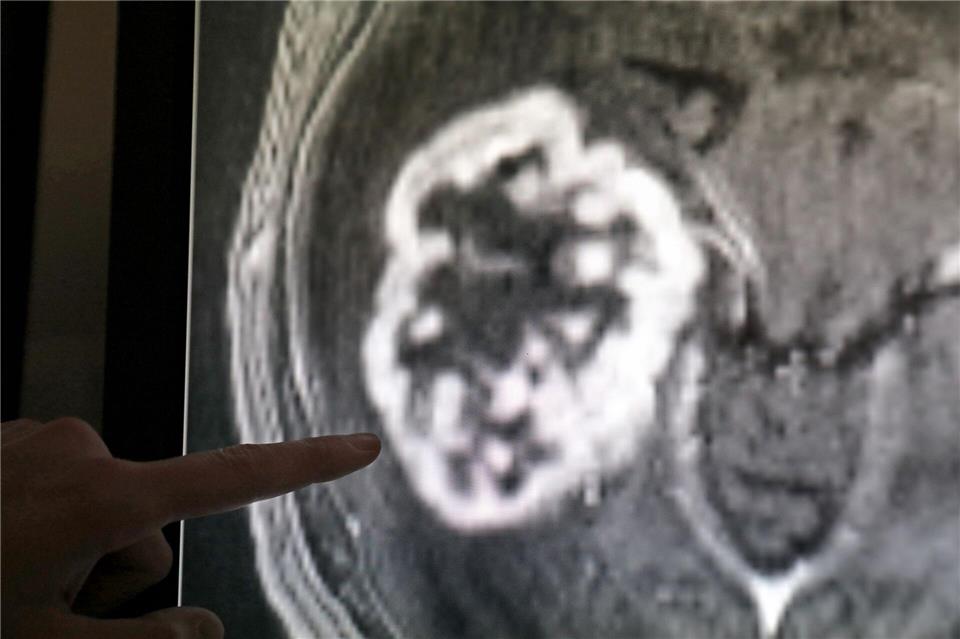

Das Krebsregister RLP erfasst seit 2016 flächendeckend stationäre und ambulante Patientendaten zu Auftreten, Behandlung und Verlauf von Tumorerkrankungen. (Symbolbild)Bernd Wüstneck/dpa-Zentralbild/dpa

Kopf-Hals-Tumoren betreffen in Rheinland-Pfalz mehr Männer als Frauen – neue Zahlen zeigen aber eine vorsichtig positive Entwicklung. Das teilte das Institut für digitale Gesundheitsdaten in Mainz mit. Demnach wurden 2024 im Bundesland 429 Männer und 213 Frauen mit Kopf-Hals-Tumoren diagnostiziert, im selben Zeitraum starben 164 Männer und 73 Frauen daran. Die Zahlen machen dem Institut zufolge deutlich, dass Männer nach wie vor häufiger betroffen sind als Frauen.